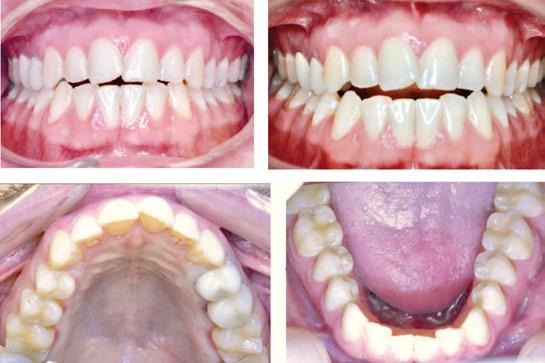

Patient S.T., age 32, presented in the hope of creating a radiant smile and a functional bite. She had been dealing with dental problems all her life. Her X-rays exhibited multiple direct restorations as well as endodontic treatment. Due to the loss of her molars, her teeth had shifted considerably over the years. Her dentist recommended she see us to create a pleasing smile and to rehabilitate her occlusion for future prosthetic treatment (Figure 8).

Diagnosis

The patient’s occlusion was super CL I on the left and CL II on the right. Both arches showed slight constriction with lower anterior crowding. Her smile arc was canted, and both midlines were shifted in opposite directions. On cephalometric

Figure 7: Case 1 progress to date — 4 months (left) and 10 months (right)

Figure 8: Case 2 initial records

Case discussion

analysis, her ANB was 5.84, and IMPA was 102.64, both representative of skeletal Class II with incisor proclination. There were two long-standing extraction sites into which the UR6 and UL6 (partial) had supraerupted. Her thin gingival mucosa posed a challenge in keeping the roots in the bone, so treatment had to be planned correctly and executed gradually to maintain her gingival architecture.

Treatment plan

Use Angel Aligner to sequentially distalize the UR and LL quadrants, correcting the AP relationship and obtaining midline coincidence (Figure 9). Intrude the supraerupted U6s to prepare the extraction sites below for implants. To preclude root resorption and fenestrations, careful attention would be paid to tooth movement velocity and the sequencing of those movements.

Case progression

At 4 months, the maxillary right side had distalized with appreciable space created between the canine and first premolar (Figure 10). At 9 months, this patient has a wide, attractive smile emerging (Figure 11). We can also appreciate the transverse

This patient’s multiple dental and occlusal issues were resolved solely with Angel Aligner. Both U6s were intruded without needing TAD support or additional mechanics to preclude labial crown torquing. Angel Aligner proved more than adequate in displacing the UR6 vertically while simultaneously distalizing it into Class I (Figure 11). To be able to intrude and distalize simultaneously with no need for TAD-supported anchorage speaks to the exceptional capability of this appliance.